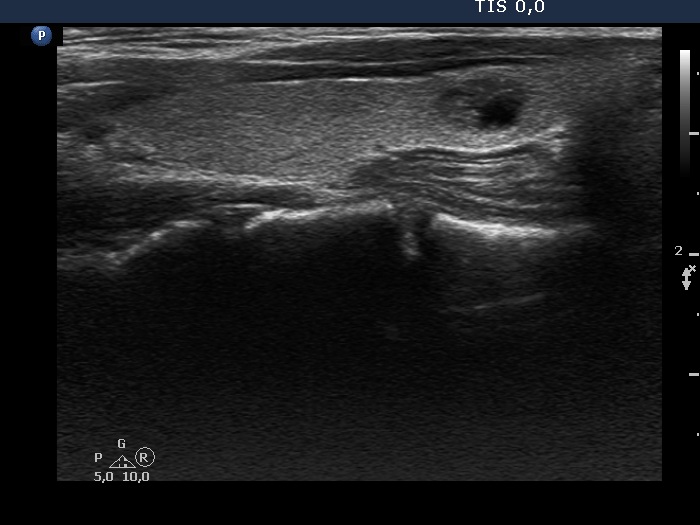

Intranodular hyperechogenic figures - case 1669 (ultrasonographic picture 5)

Left lobe, longitudinal scan. There is a small cystic-moderately hypoechogenic lesion in the lower-central part of the lobe.